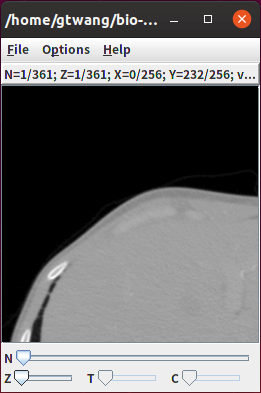

如果影像解析度很高,也可以用 -crop 切割影像區域,只顯示部份影像,切割區域的設定方式為 x,y,width,height,其中 x 與 y 為切割區域的左上角座標,而 width 與 height則為切割區域的寬度與高度,例如:

# 僅顯示部份區域

showinf -crop ,,256,256 image.dcm

若要切割影像區域,可以使用 -crop 參數,切割區域的設定方式為 x,y,width,height,其中 x 與 y 為切割區域的左上角座標,而 width 與 height則為切割區域的寬度與高度,例如:

# 僅轉出部份影像區域

bfconvert -crop ,,256,256 input.dcm output.tiff